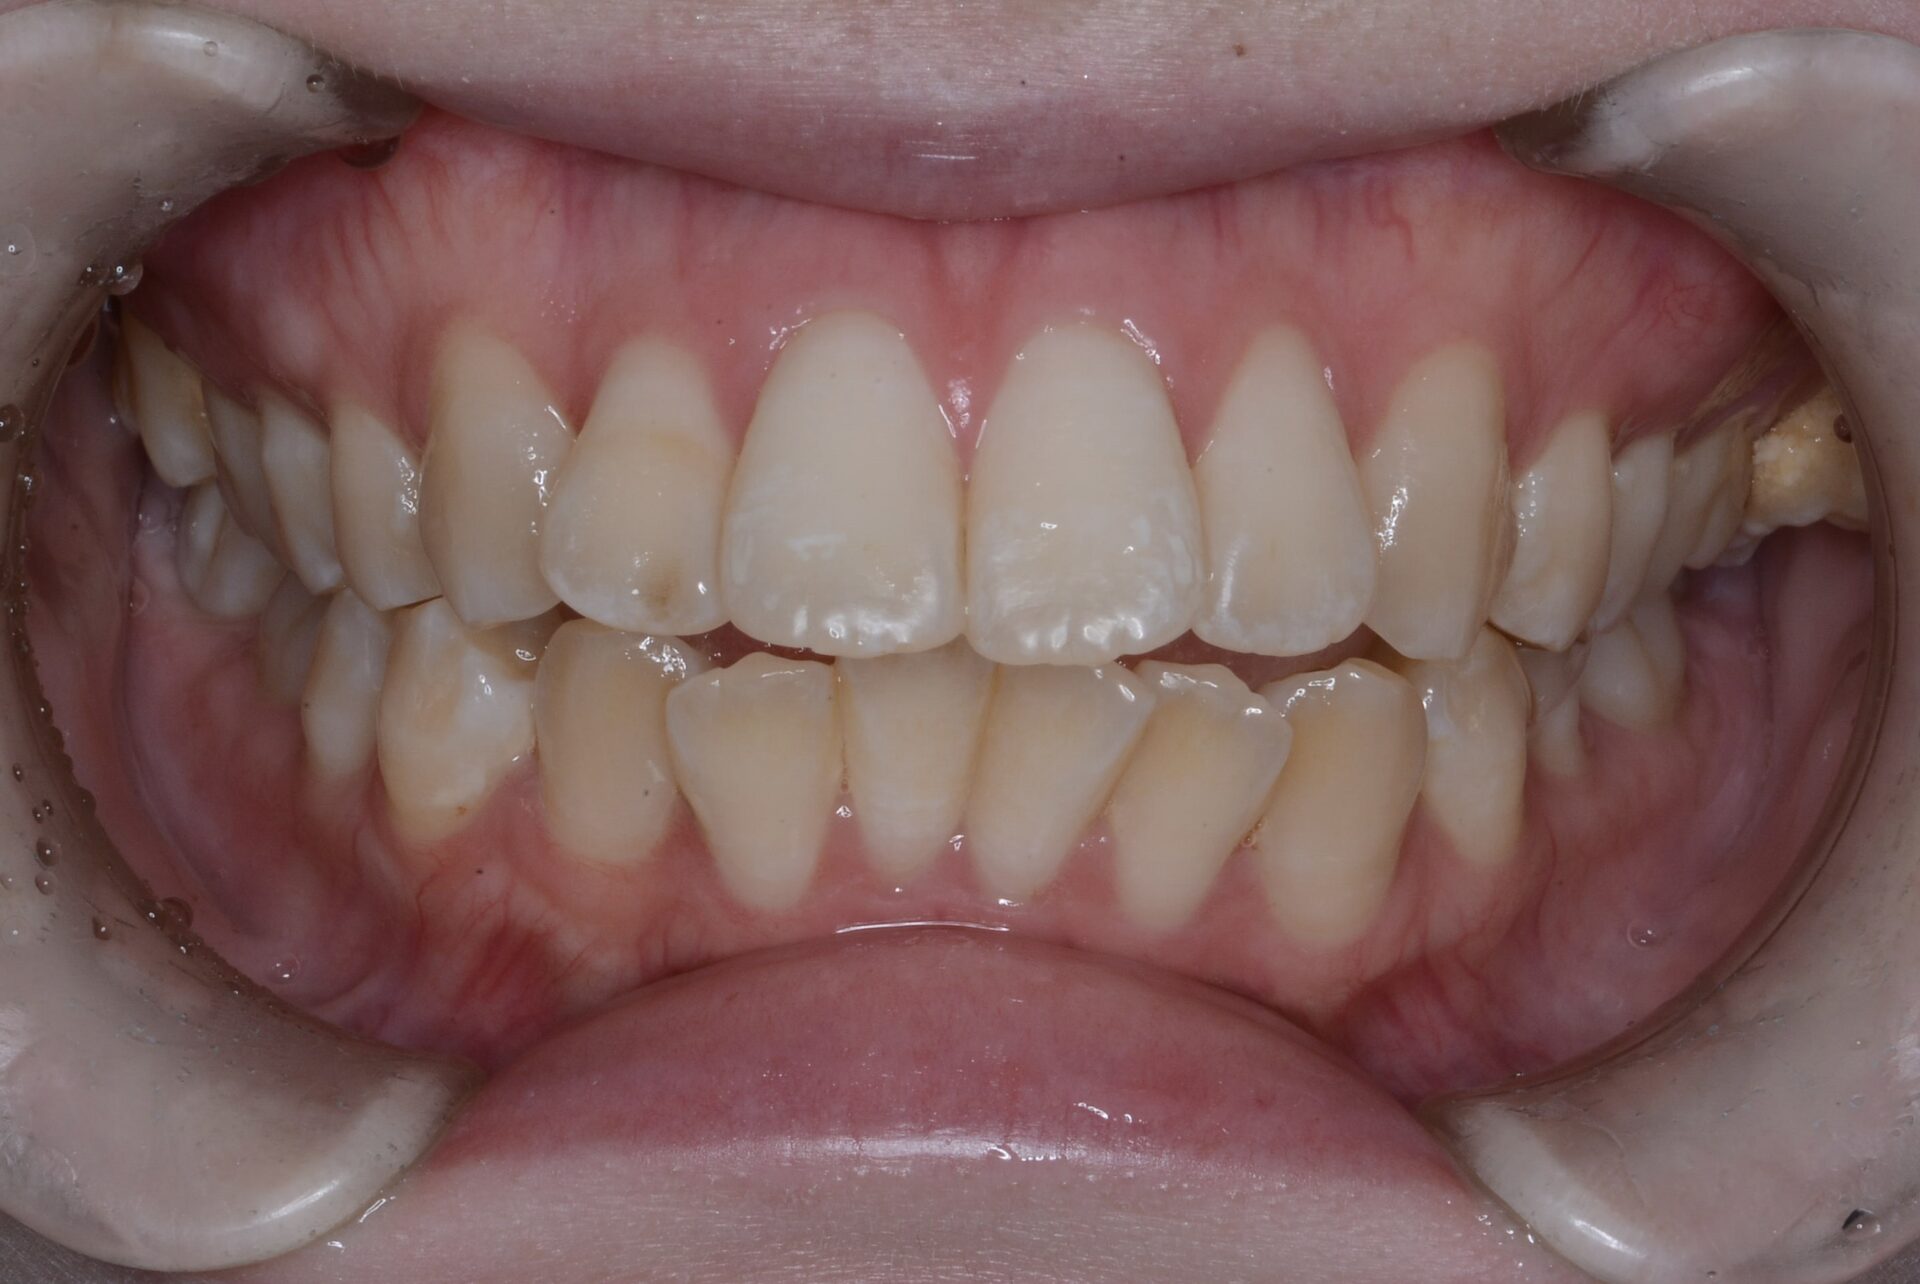

初診時

奥歯だけが点で当たっていて、前歯が噛んでいない。

左側上顎第2大臼歯が随分と外側に生えている。そのため下顎とすれ違ってしまっていた。